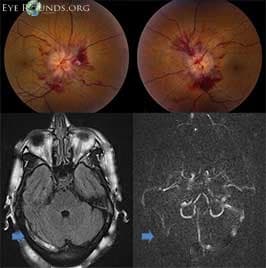

Clinical Images

High-resolution clinical photographs showing various presentations of optic neuritis.

Optic neuritis is inflammation of the optic nerve. It can cause sudden vision loss and pain with eye movement. It is often the first sign of Multiple Sclerosis (MS).

An MRI of the brain helps determine your risk of developing Multiple Sclerosis.